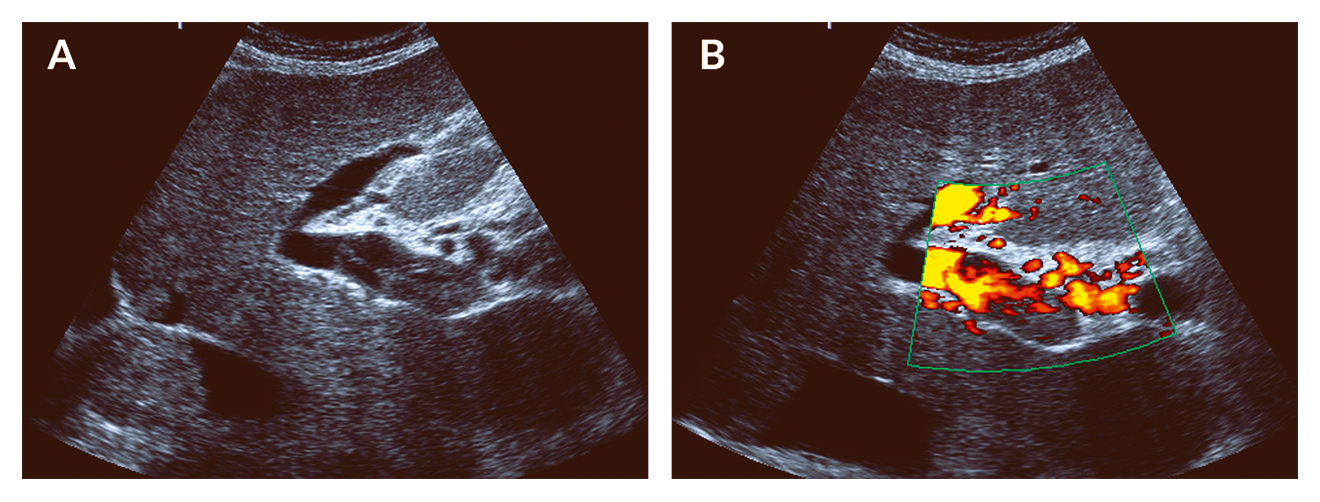

Both acute PVT and portal cavernoma are easily detected using sonography, CT or MR imaging. Acute PVT presents as intraluminal hyperechoic material in ultrasound, while Doppler imaging demonstrates a lack of blood flow (Figure 3). Using contrast-enhanced ultrasound (CEUS), vascularisation of the thrombus may be used to identify malignant thrombi. As PVT may extend to the mesenteric or splenic veins, thorough assessment of the splanchnic tributaries is mandatory. For detailed assessment of thrombus extension, CT or MR angiography are more sensitive than Doppler sonography.

Figure 3. Acute portal vein thrombosis. Ultrasound of a patient with acute PVT. (A) Hyperechoic material is located within the main portal vein. (B) Using the power mode for flow detection, blood flow is limited to those parts of the portal vein without hyperechoic material